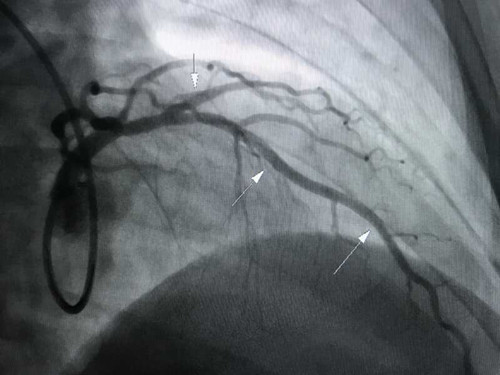

我院首例冠状动脉造影检查显示左右冠状动脉均有狭窄,最重处达到90%,成功放置三枚支架,效果佳。

第一张图示三处狭窄,第二张图示支架术后狭窄解除。血运通畅,病人及家属非常感激。我院引进的德国西门子DSA先进高端、手术射线量统 计 了一下,只相当于做一次头颅CT。我院收费合理,同样手术要比其他医院优惠2万多元。为前来就医的患者提供质优价平的真诚服务。同时减少病人往返徐州的麻烦及花销。我院全体职工本着“病人好,我才好”的服务理念,励精图治,满腔热忱的为人民群众提供优质的医疗服务。